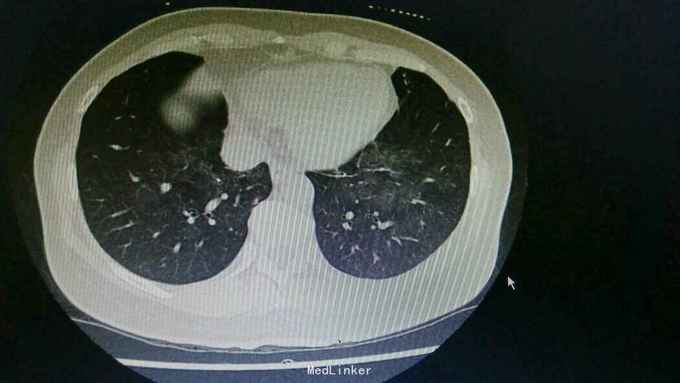

主诉:咳嗽8天,咯血6天。 病史:患者自诉8天前无明显诱因出现咳嗽,为刺激性干咳,未予以处理,6天前出现咯血,具体量不祥,为求诊治,入住我科。

查体:右下肺闻及湿性啰音,余无特殊。 辅查:胸部CT:右肺中上叶支扩并感染,双肺下叶磨玻璃影,考虑肺泡内积血可能。

诊断:支扩并咯血。 治疗:入院予以抗感染,止血,止咳化痰等治疗。